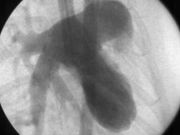

ラット生体脳血管X線動画です。